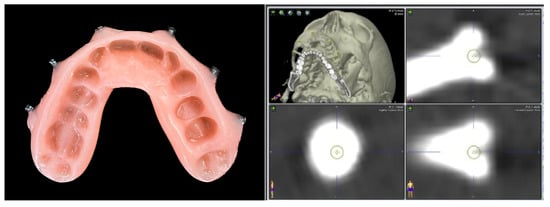

- Non-invasive fiducial markers: specific occlusal dental splints in which radiopaque landmarks are placed in such a way that they can be worn during the CT scan acquisition and used as non-invasive fiducial markers. It is an easy technique, but it requires the additional time to fabricate the splint. It cannot be used in edentulous patients, and its accuracy tends to be reduced above the plane passing through the orbital floor. The splint can be safely removed after registration and re-used during surgery and if the recording has to be repeated to verify the post-operative accuracy.

| Case 2 Impacted teeth in Pfeiffer Syndrome | 0.5 mm | 0.3 mm | 0.6 mm | |

| Case 3 Impacted teeth in Apert Syndrome | 0.3 mm | 0.5 mm | 0.4 mm | 0.5 mm |

| Case 4 Impacted teeth | 0.3 mm | 0.2 mm |